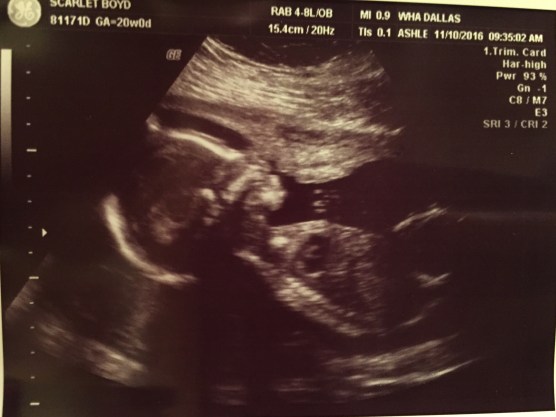

Now back to our bumpdate. We had two appointments last week: one with our OB and one with your MFM specialist. First up, our 20 week appointment with my OB. This appointment was a lot of fun! I pretty much live at the doctor’s office so I’ve become close with a lot of the staff which makes things easier…especially while sitting in a room with your belly exposed & someone running a wand over it for 30+ mins. Crockett was very active during the sono so I got to see him twist and turn all over the place . At one point it looked like he was waving at us and the sono tech said “Look! He’s got a great Miss America wave going on” and right away he elbowed her hand twice which made us giggle. Okay little man, it was a tough guy wave :). Crockett was measured for everything possible as well as checking the placenta, cord insertion, and cord blood flow. He passed every test and his growth looks great! He has doubled his weight since our last appointment to a whopping 12 ounces. He looks so big on the screen but the weight always brings me back to reality, he is so tiny right now.

They quickly got me into an exam room and the sonographer came in immediately. I don’t know if this was to sooth me or to double check he still had a heartbeat. Probably both because I’m usually waiting in that room for about 10 minutes. Once hooked up, he was doing his usual morning calisthenics. I swear, mornings are his jam. He constantly parties in the morning! This appointment we double checked all of his growth and compared it to last month. He’d grown well in all categories and they confirmed his stout 12 ounce weight. We spent a lot of time checking the placenta and his cord. It looked like he was using the placenta as a pillow…just laying his head right on top of it. He continued to wiggle the entire appointment. The sonographer called him a “wild man”, hehe! My MFM doctor came in next to continue with the sonogram and confirm everything the sonographer saw. He said Crockett is growing like a weed and couldn’t be more pleased with his progress. He also checked on my mental health. I love that he does this each appointment because he reminds me at this point to not be polite nor to sit at home scared if I think something is wrong. I told him if/when I become upset, he’d know it :).

Thank you to everyone who has prayed over us or asked how we’re doing these past 2o weeks. Your thoughtfulness and kindness is never lost on us. The support we have received lifts our hearts and strengthens our minds. I hope you enjoy some of the latest pictures of our growing boy!

This is a video of the sonogram at our specialist. They give us a video each time of the entire sonogram which I treasure. They are the only visual proof I had of Cora when she was still alive and I am thankful to have each one of Crockett. In this video, you can see him playing with his hands in front of his face before they take his heart rate. It’s incredible what they get up to in the womb!